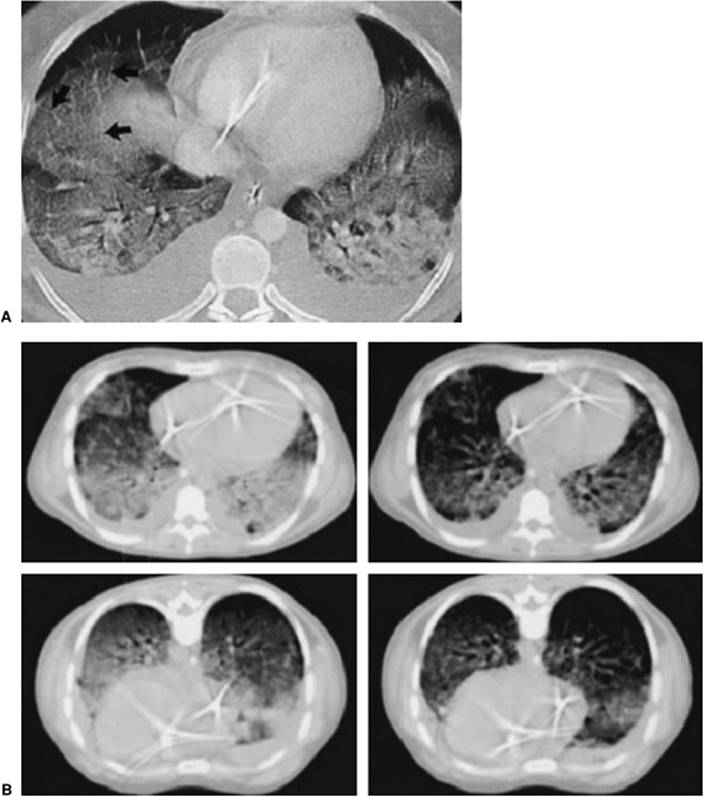

Figure 136.2. Diffuse interstitial and panacinar infiltrates are seen in a 36-year-old patient with acute respiratory distress syndrome. Also notice one of the complications of the respiratory support—a right mainstem intubation.

The changes seen on the chest radiograph in ARDS are characteristic but nonspecific, rarely revealing the etiology of the syndrome. Acutely, pulmonary edema is seen. Interstitial infiltrates progress to a diffuse, fluffy, panacinar pattern (Fig. 136.2). Although it may be difficult to differentiate from cardiogenic pulmonary edema, there is generally an absence of pulmonary vascular redistribution, pleural effusion, or cardiomegaly. The panacinar infiltrates may consolidate and, with time, take on a patchy or nodular pattern. If the patient improves, radiographic results may revert to normal. If the disorder progresses, a pattern of diffuse interstitial fibrosis may ensue (Fig. 136.3).

Therapeutic interventions may alter the radiographic findings. Pulmonary infiltrates may increase with injudicious fluid administration. Positive pressure ventilation and PEEP may lead to hyperinflation, and subcutaneous, mediastinal, retroperitoneal, and intraperitoneal emphysema, or pneumothorax. Mainstem bronchus intubation may lead to ipsilateral pneumothorax or contralateral lung collapse (Fig. 136.4).

Figure 136.3. A pattern of diffuse interstitial fibrosis has developed in this 52-year-old patient with acute respiratory distress syndrome.

Figure 136.4. This 70-year-old patient with acute respiratory distress syndrome has a right tension pneumothorax and right mainstem intubation.

Whereas a two-dimensional chest radiograph may suggest diffuse homogeneous infiltrates, the chest computed tomography (CT) scan usually demonstrates remarkably inhomogeneous lung involvement. Dependent regions of the lung appear to be much more involved than nondependent regions. Although chest CT scanning is not always practical in the day-to-day management of patients with ARDS, in investigational trials, it has provided a vivid image of dramatically reduced lung volumes. The chest CT also may be useful in demonstrating the presence and magnitude of pneumothoraces and pleural effusions not well visualized on the standard chest radiograph. It is also useful for the positioning of thoracostomy tubes in patients with loculated pneumothoraces.

Lung CT studies have demonstrated the distribution of areas of alveolar collapse and distention characteristic of ARDS to be regional rather than diffuse. Alveolar collapse predominates in dependent areas, producing venous admixture and hypoxemia, while nondependent areas manifest airway destruction with hyperinflation, often to the point of exclusion of pulmonary capillary blood flow (dead space) (62,63). These alveolar morphologies, however, are not strictly related to dependency within the chest cavity, as is clearly visible in Figure 136.5. Areas of atelectasis, producing shunt (solid arrows) and airway/alveolar destruction, and areas of overdistention, producing dead space (dashed arrows), may be randomly distributed and interspersed with areas of spared pulmonary tissue, thereby generating profound ventilation/perfusion mismatch.

000156

Figure 136.5. Computed tomography scan of the chest of a patient with acute respiratory distress syndrome. Solid arrows show dense parenchymal opacification resulting in shunt. The broken lines show relatively “normal”-appearing lung but that can suffer from overdistention, resulting in dead space. (With permission from Desai SR. Acute respiratory distress syndrome: imaging of the injured lung. Clin Radiol. 2002;57[1]:8–17.)

Figure 136.9. A: Consolidated lung in a patient with acute respiratory distress syndrome. Note the air bronchograms and dependent consolidation. (With permission from Ware LB, Matthay MA. The acute respiratory distress syndrome. N Engl J Med. 2000;342[18]:1334–1349.) B: Improvement in dependent consolidation once proning has occurred. (With permission from Pelosi P, Brazzi L, Gattinoni L. Prone position in acute respiratory distress syndrome. Eur Respir J. 2002;20[4]:1017–1028.)